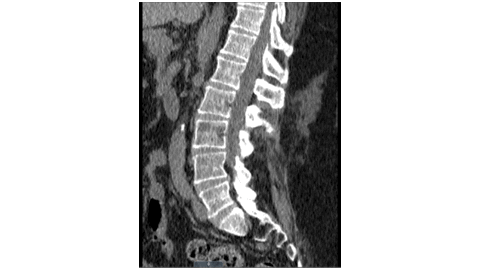

We present a case of spinal hemangioma with clinical presentation with lower limb weakness, loss of sensation, back pain, urinary retention and difficulty in bowel movements for 9 months. Patients presenting with lumbar myeloradiculopathy should be carefully evaluated to distinguish it from cauda equina syndrome, spinal dural fistula, spinal cord tumors, and metastasis. Evaluation including MRI brain and CT scan lumbar spine were within normal limits. Further workup including CT scan and MRI thoracic spine revealed T5 vertebral body spinal hemangioma with spina cord compression at T5-T6. The main pathology here is slowly progressive tumor that had power to scrunch the spinal cord and shatter the vertebra, thereby ushering the onset of myeloradiculopathy. Neurosurgery was consulted and they decided to perform a preoperative embolization, and surgical decompression. Recurrence of symptoms despite surgical intervention might necessitate administration of radiation therapy. The neuronal recovery following surgery might be prolonged given the degree of spinal cord injury.